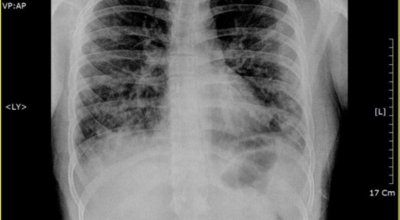

초기에 가벼운 기침으로 시작해 호흡하는 것조차 힘들어지게 되는데요 폐에 발생한 염증으로 인해서 폐의 신전성이 감소하고, 폐를 구성하는 폐포 세포가 망가져 적정 수준의 산소를 보관하지 못하기 때문에 호흡곤란이 유발될 수 있어요.